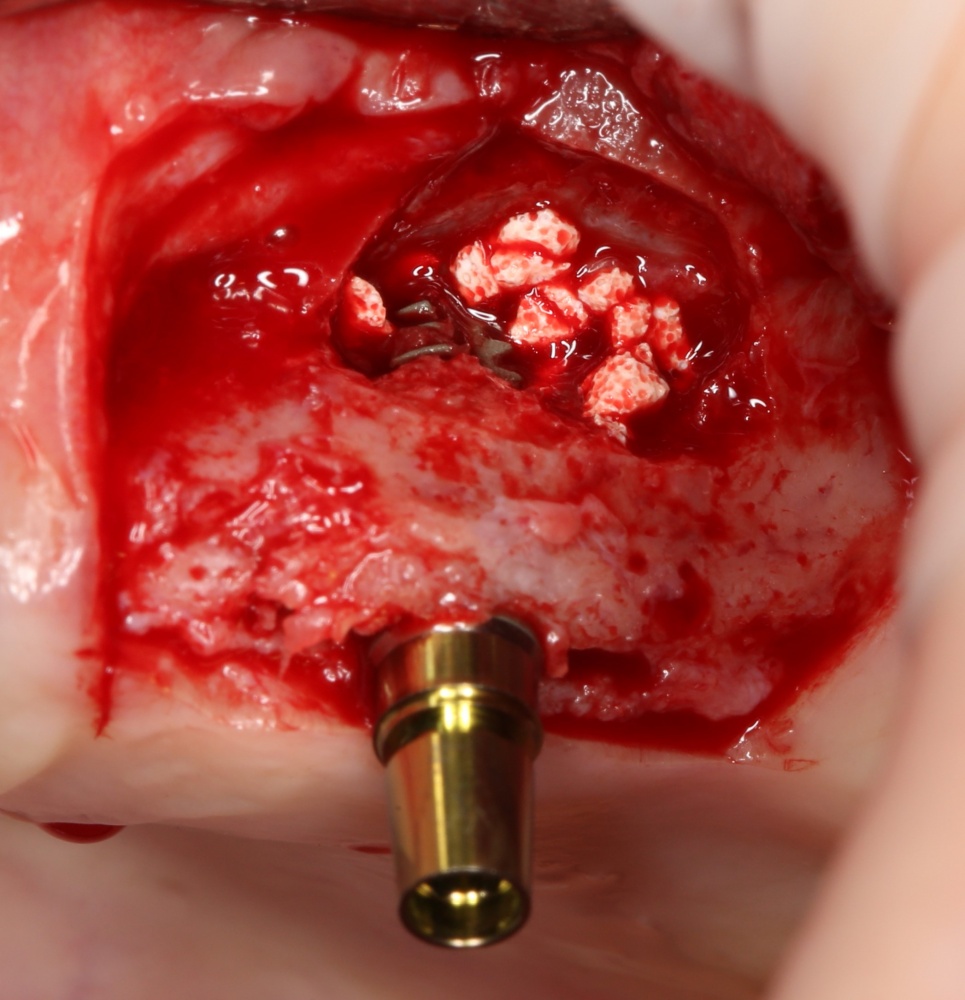

Простой синуслифтинг. Часть I.